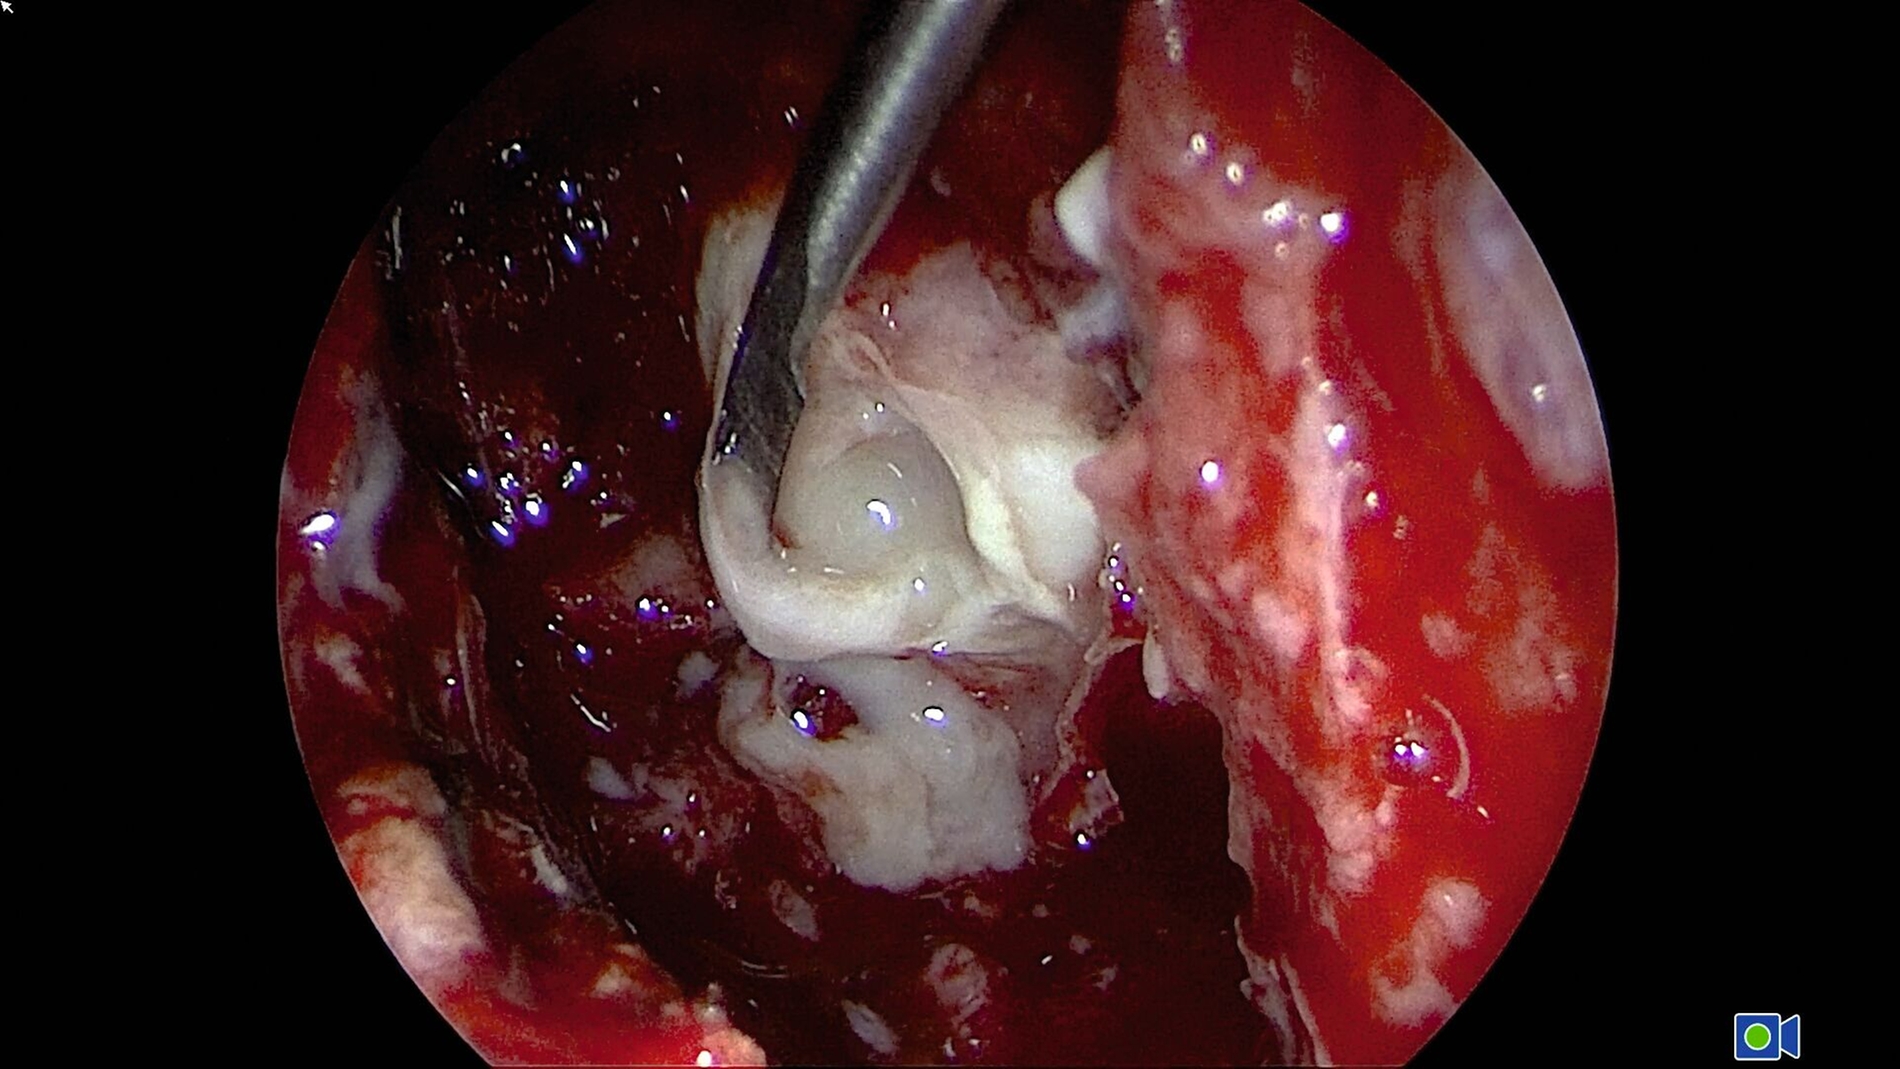

Während der Anmeldungen und Konsilanforderungen wurde notfallmäßig in Lokalanästhesie der in situ verbliebene Wurzelrest 25 mittels Osteotomie entfernt und die Kieferhöhle über die Alveole eröffnet. Das Kieferhöhlenempyem wurde entlastet und ein Drainageröhrchen eingelegt. Es kam zu reichlich Abfluss übelriechenden Eiters (Abbildung 5) und zur merklichen Entlastung für die Patientin. Es wurden Abstriche für die mikrobiologische Untersuchung genommen und die Kieferhöhle wurde wiederholt mit NaCl gespült.

Anschließend wurde am selben Abend eine endonasale endoskopische Nasennebenhöhlenoperation links mit Uncinektomie, Kieferhöhlenfensterung Typ 3, anteriorer Ethmoidektomie und transethmoidaler Entlastung des Orbitaabszesses durchgeführt (Abbildung 7). Intraoperativ zeigte sich neben dem subperiostalen Abszess auch eine intraorbitale Abszesskomponente jenseits der Periorbita.